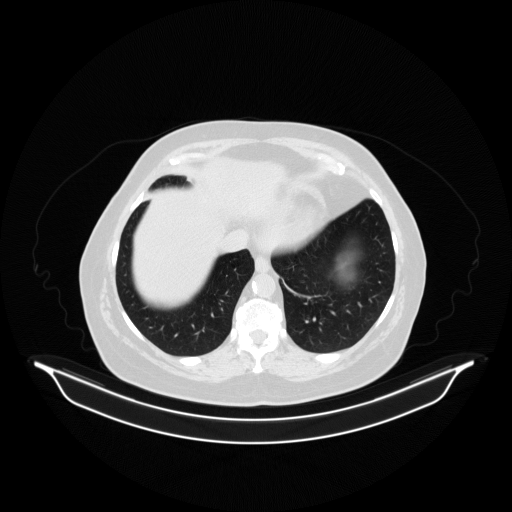

Original VENOUS CT scan

Lung window (WL -600, WW 1500 β†’ Low βˆ’1350, High +150)